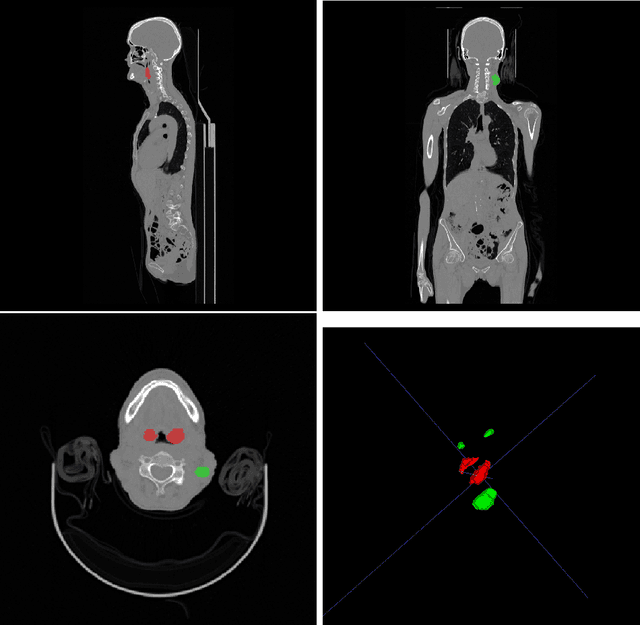

Head and neck tumor segmentation challenge (HECKTOR) 2022 offers a platform for researchers to compare their solutions to segmentation of tumors and lymph nodes from 3D CT and PET images. In this work, we describe our solution to HECKTOR 2022 segmentation task. We re-sample all images to a common resolution, crop around head and neck region, and train SegResNet semantic segmentation network from MONAI. We use 5-fold cross validation to select best model checkpoints. The final submission is an ensemble of 15 models from 3 runs. Our solution (team name NVAUTO) achieves the 1st place on the HECKTOR22 challenge leaderboard with an aggregated dice score of 0.78802.